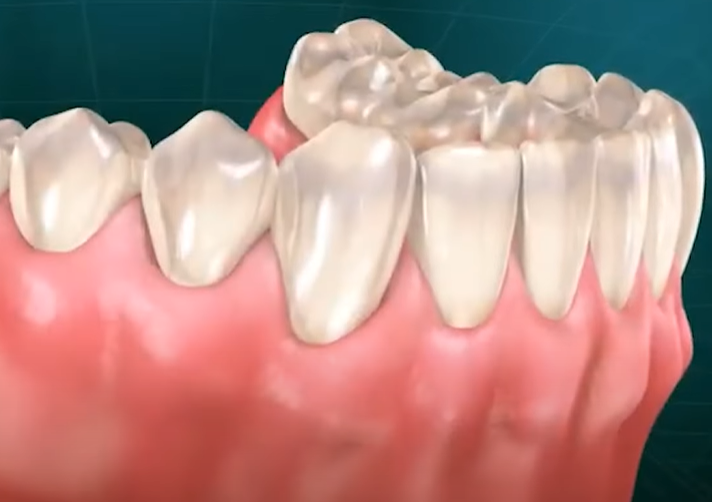

치주염과 잇몸 내려 앉음 [잇몸퇴축]

치주염은 잇몸의 주요 질환으로, 치조골(잇몸을 지지하는 뼈)을 파괴합니다.

잇몸은 치조골의 상태를 따라가므로, 치조골이 손상되면 잇몸도 함께 퇴축하게 됩니다.